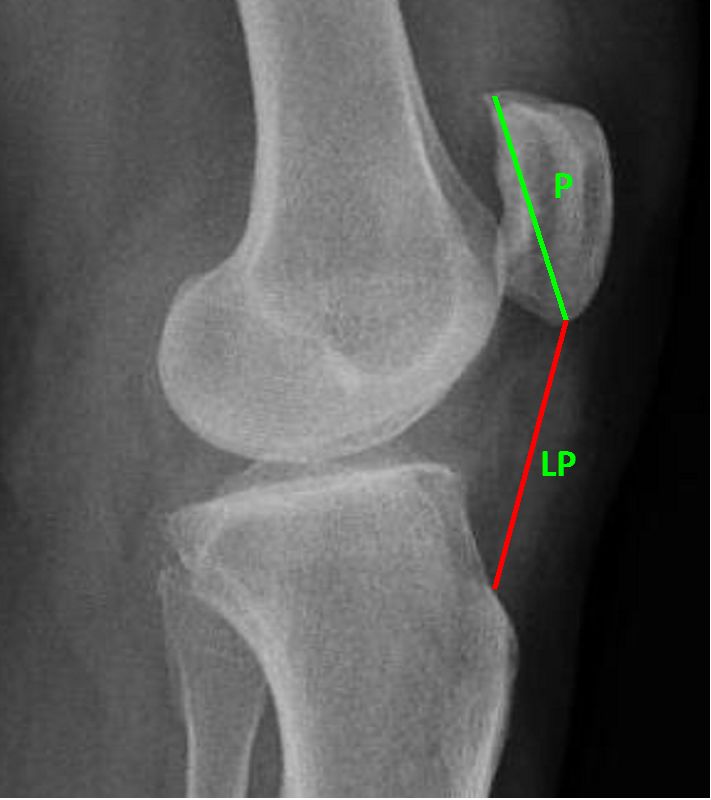

Как и при любой травме коленного сустава для постановки правильного диагноза выполняется рентгенография, на которой-то и можно увидеть перелом. Обычно рентгенографию выполняют в прямой и боковой проекциях, а для диагностики вертикальных переломов выполняют еще и осевую (аксиальную, или Merchant) проекцию.

Прямая (слева) и боковая (справа) проекции, на которых виден горизонтальный перелом надколенника со смещением отломков. Осевая проекция. Вертикальный перелом. Обратите внимание на возникшую в результате смещения ступеньку на скользящей поверхности надколенника.

Для подтверждения диагноза необходимо выполнить рентгеновские снимки в двух проекциях, иногда требуется выполнение аксиальной проекции, особенно при вертикальных переломах. Обычно, перелом надколенника хорошо виден на рентгеновских снимках.

На рентгенограмме показан перелом тела надколенника без смещения.

На рентгенограмме продемонстрирован перелом нижнего полюса надколенника.

Перелом надколенника слева со смещением отломков. Необходима операция.

Краевой перелом надколенника, хорошо видимый на аксиальной рентгенограмме.